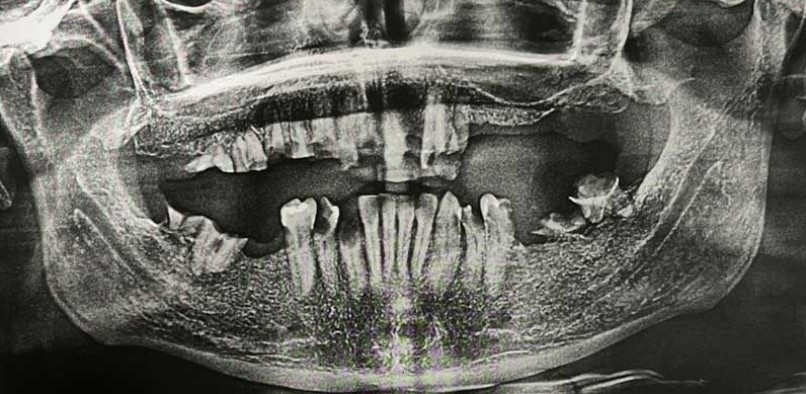

Oriol: Paciente de 32 años acude a la consulta para la valoración de su estado critico dental.

Le explicamos que es un paciente con caries recidivante, que sus dientes constantemente tienen caries y que es inviable conservar sus dientes.

Se le da la opción de realización de la técnica “all on four”, técnica implantología y rehabilitadora que consiste en substituir todos los dientes de uno de los maxilares del paciente por 12 coronas de metal cerámica que se sustentan sobre 4 implantes. El paciente accede a la extracción de sus deteriorados dientes, hacer la técnica “all on four” en maxil·lar y mandíbula y la colocación de unos provisionales fijos. Todo ello se realiza en una cirugía de 4 horas en la que el paciente estará sedado.